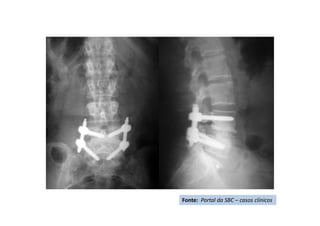

Radiografia pós-operatório -AP

Fonte: Portal da SBC – casos clínicos

Radiografia pós-operatória

- PERFIL

Resultado clínico pós operatório -

AP

Resultado clínico pós operatório

- lateral